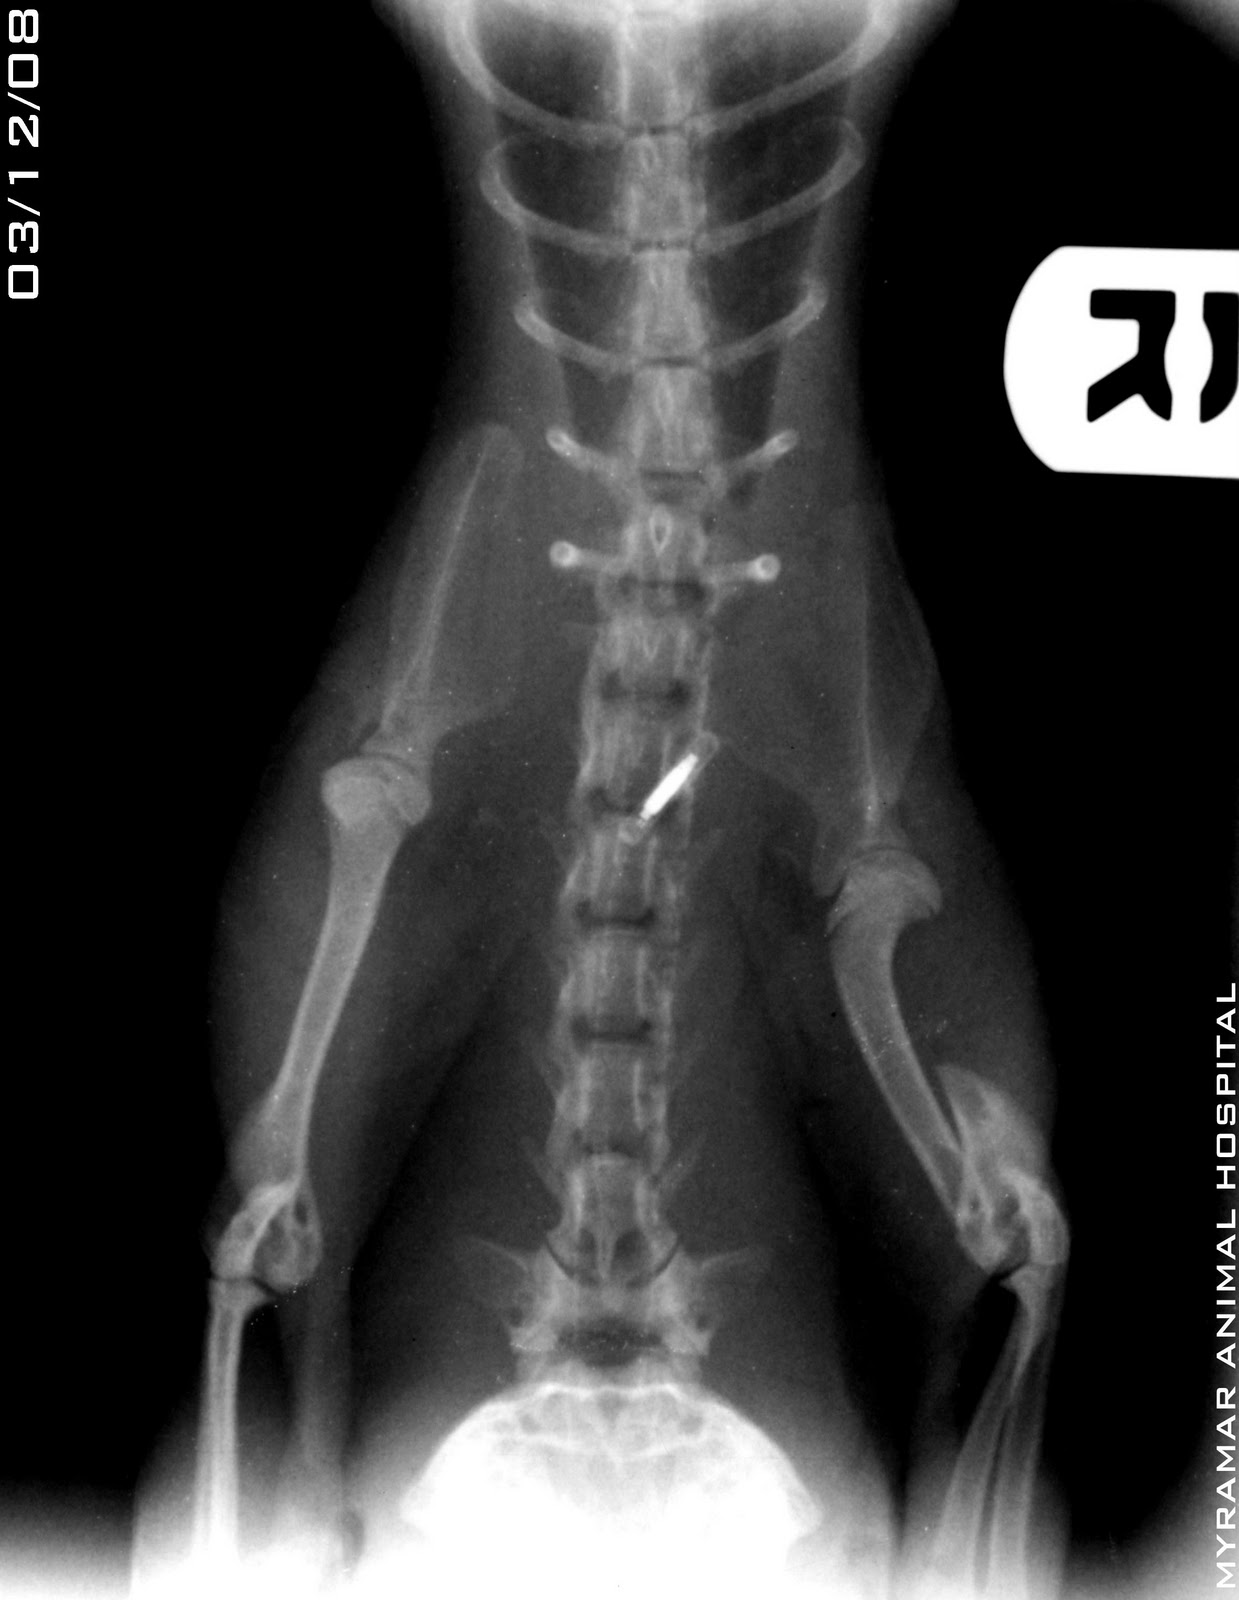

aBruno, hurón de 7 meses de edad y 900 gramos de peso se presenta en consulta con fractura diafisaria humeral oblícua, Class AOVET: 12-A3.

Se reduce la fractura utilizando Tie-in, con aguja centromedular y 2 agujas (en zona proximal y distal), todo únido externamente mediante PMMA.

Se presentan radiografías pre y postoperatorias así como dinamización del sistema y evolución en el tiempo.